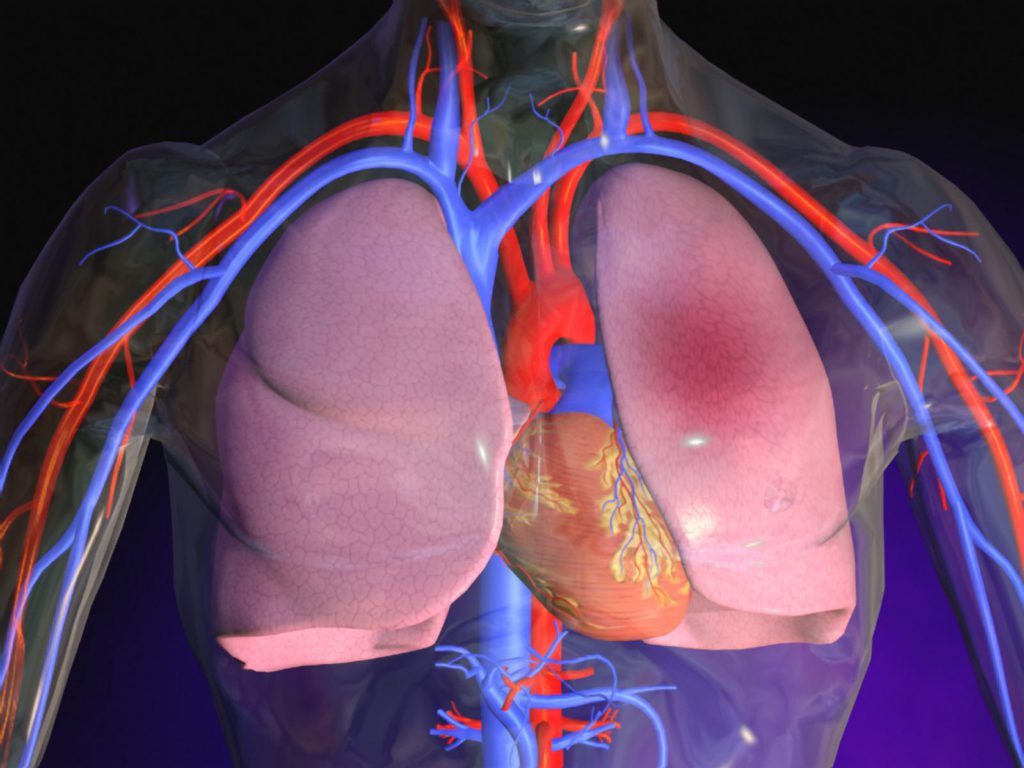

Остановка движения тромба может происходить в крупных сосудах, которые переносят жидкую соединительную ткань от легких к сердцу, а также в их ответвлениях. Последствия зависят от числа «плавающих» частиц и их размеров. Чем больше тромбы, тем выше вероятность полного перекрытия жизненно важных артерий.

Тромбы могут образовываться не только в нижних конечностях и области таза, но и в правом предсердии, а также в верхних конечностях, хотя такие случаи встречаются реже. Механизм прост: при повреждении верхнего слоя сосудов открывается следующий, что способствует более быстрому свертыванию крови, и к этому участку присоединяются другие частицы.